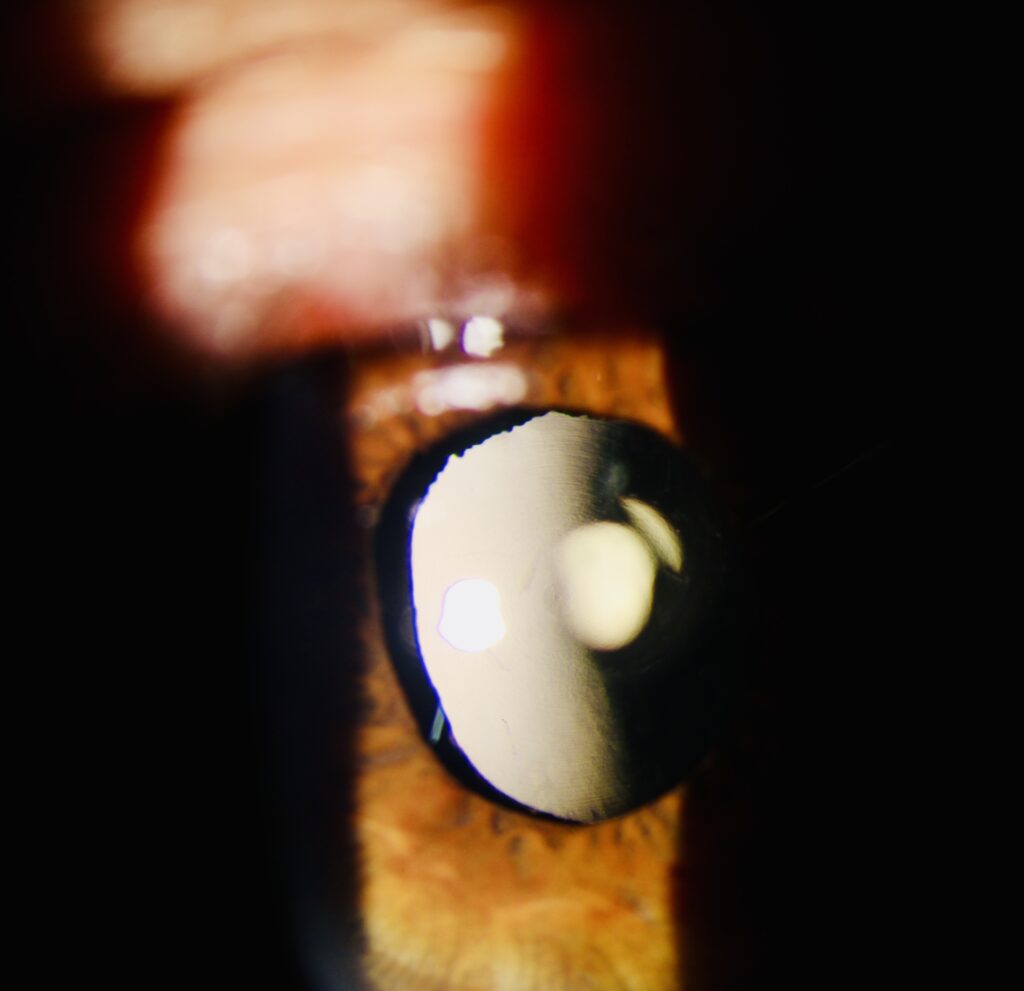

Como é feita a cirurgia de catarata?

A cirurgia é rápida, segura e realizada com anestesia local (colírio) e sedação leve. Dura cerca de 10 a 20 minutos e é feita com alta tecnologia. Utilizamos o método de facoemulsificação, no qual o cristalino opaco é fragmentado por ultrassom e substituído por uma lente intraocular.

O tipo de lente é escolhido conforme seu perfil visual, estilo de vida e necessidades específicas. Essa escolha é parte essencial da consulta, pois impacta diretamente no resultado final.

Etapas da cirurgia:

1. Realiza-se uma pequena incisão na córnea.

2. O cristalino opaco é fragmentado com tecnologia de facoemulsificação (ultrassom) e aspirado.

3. Em seguida, é implantada uma lente intraocular no lugar do cristalino.